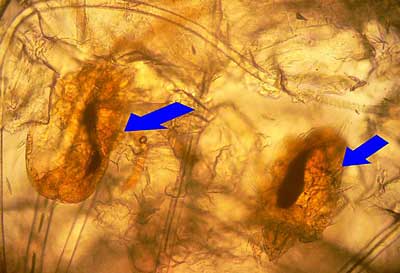

D’autres prélèvements cutanés permettent de retrouver des larves de trombicula automnalis vivantes.

Photo 8